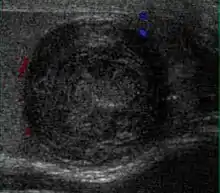

However, these patterns, except the latter one, may be considered as non-specific as heterogeneous echotexture and shadowing calcification can also be detected in malignant testicular tumors. The onion peel pattern of epidermoid cyst [Fig. 10] correlates well with the pathologic finding of multiple layers of keratin debris produced by the lining of the epidermoid cyst. This sonographic appearance should be considered characteristic of an epidermoid cyst and corresponds to the natural evolution of the cyst. Absence of vascular flow is another important feature that is helpful in differentiation of epidermoid cyst from other solid intratesticular lesions.

Teratoma Although teratoma is the second most common testicular tumor in children, it affects all age groups. Mature teratoma in children is often benign, but teratoma in adults, regardless of age, should be considered malignant. Teratomas are composed of all three germ cell layers, i.e. endoderm, mesoderm and ectoderm. At ultrasound, teratomas generally form well-circumscribed complex masses. Echogenic foci representing calcification, cartilage, immature bone and fibrosis are commonly seen [Fig. 5]. Cysts are also a common feature and depending on the contents of the cysts i.e. serous, mucoid or keratinous fluid, it may present as anechoic or complex structure [Fig. 6].

Fig. 5. Teratoma. A plaque-like calcification with acoustic shadow is seen in the testis.